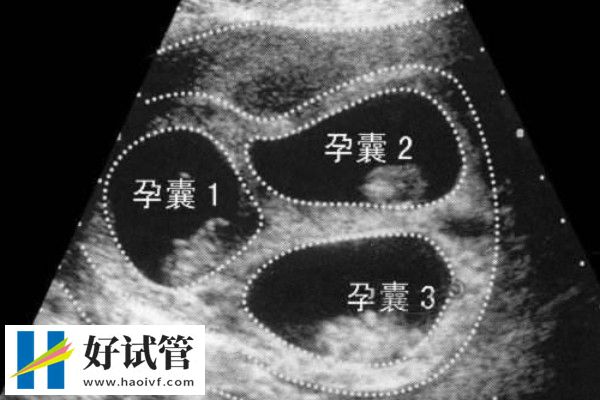

试管婴儿胚胎移植是将在实验室内进行体外授精后,在培养皿中培养形成的早期胚胎移植回准妈妈的子宫内,使早期胚胎可以在母体内继续生长发育的过程。

攒胚胎指将取卵后获得的胚胎通过冷冻技术保存起来,在适当的时候再进行移植。这包括玻璃化冷冻法和程序冷冻法,旨在保护胚胎的生命力,使其处于休眠状态。而养囊指将取卵后获得的胚胎继续培养至囊胚阶段,再进行移植。囊胚是胚胎进一步发育的产物,通常在卵子受精后的第五到七天形成。